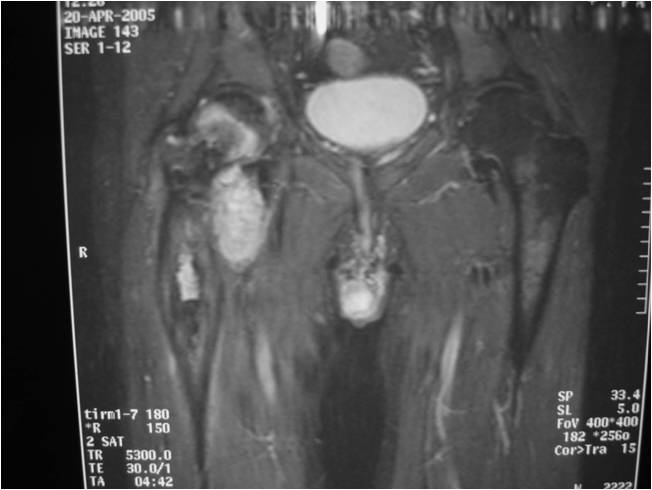

Sites:

- Most common in pelvis, proximal femur, proximal humerus, distal femur, ribs

- Similar sites as conventional chondrosarcoma

Radiographic Presentation

Radiology emulates pathology: Biphasic Tumor

- One region low grade chondrosarcoma

- Second more aggressive area with bone destruction, lysis of calcification, soft tissue mass

- Cortical permeation and a soft tissue mass in 70% of cases

Ill-defined, lytic intraosseous lesion

- Or extraosseous soft tissue mass

- Devoid of calcifications in continuity with lesions having the features of a cartilaginous tumor

Characteristically abrupt transition between chondroid tumor and dedifferentiated, lytic component

Bone may be expanded and adjacent cortex thickened

(Right Arrow)Aggressive Lytic Area (Dedifferentiated Sarcomatous Component) Cortical Destruction Soft Tissue Mass without Calcification